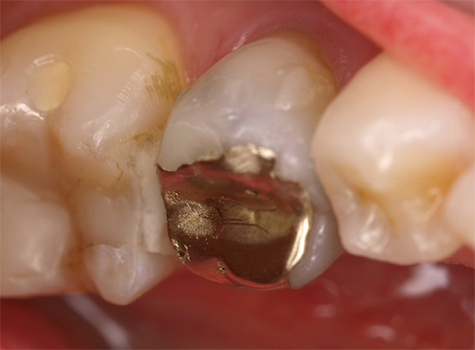

Bovendien biedt Futurabond U het beslissende voordeel dat het een betrouwbare hechting zonder extra primer ook aan diverse materialen als metaal, zirkoon-, aluminiumoxide en silicaatkeramiek waarborgt. Daarom is het op een bijzondere manier ook geschikt voor intra-orale reparaties. De foto’s 7-9 laten een typische klinische casus zien, waarbij het behoud van de aanwezige gouden restauratie gepaard ging met de reparatie van harde tandsubstantie. Hier is het goede hechtende vermogen van het adhesief aan compleet verschillende materialen de voorwaarde voor een succesvolle en duurzame restauratie.

Afb. 7: Applicatie van Futurabond U op gouden restauratie en harde tandsubstantie

Afb. 8: Applicatie van een vloeibaar composiet

Afb. 9: Toestand na succesvolle reparatie